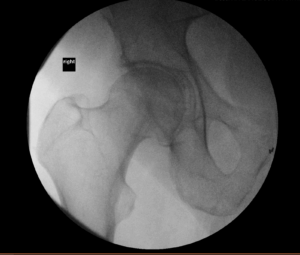

Almost had a replay this week of that incident a year ago. A nurse asked me to go with him for an injection into his hip joint. Long, big-gauge needle into the center of the joint, all visible on live-action X-ray. I told myself I wouldn’t look at the screen.

But then the doctor said I couldn’t stay in the room. She’d once had a family member faint and fall to the floor during the procedure. At that point, she had two patients instead of one.

So I waited out in the hall. Afterwards, Bob said it had gone fine, didn’t hurt all that bad. And it has helped him. He’s feeling a bit better, though still not going out for track. (Above, one of my favorite pictures of him, celebrating our 15th anniversary. We’re now at 42.)